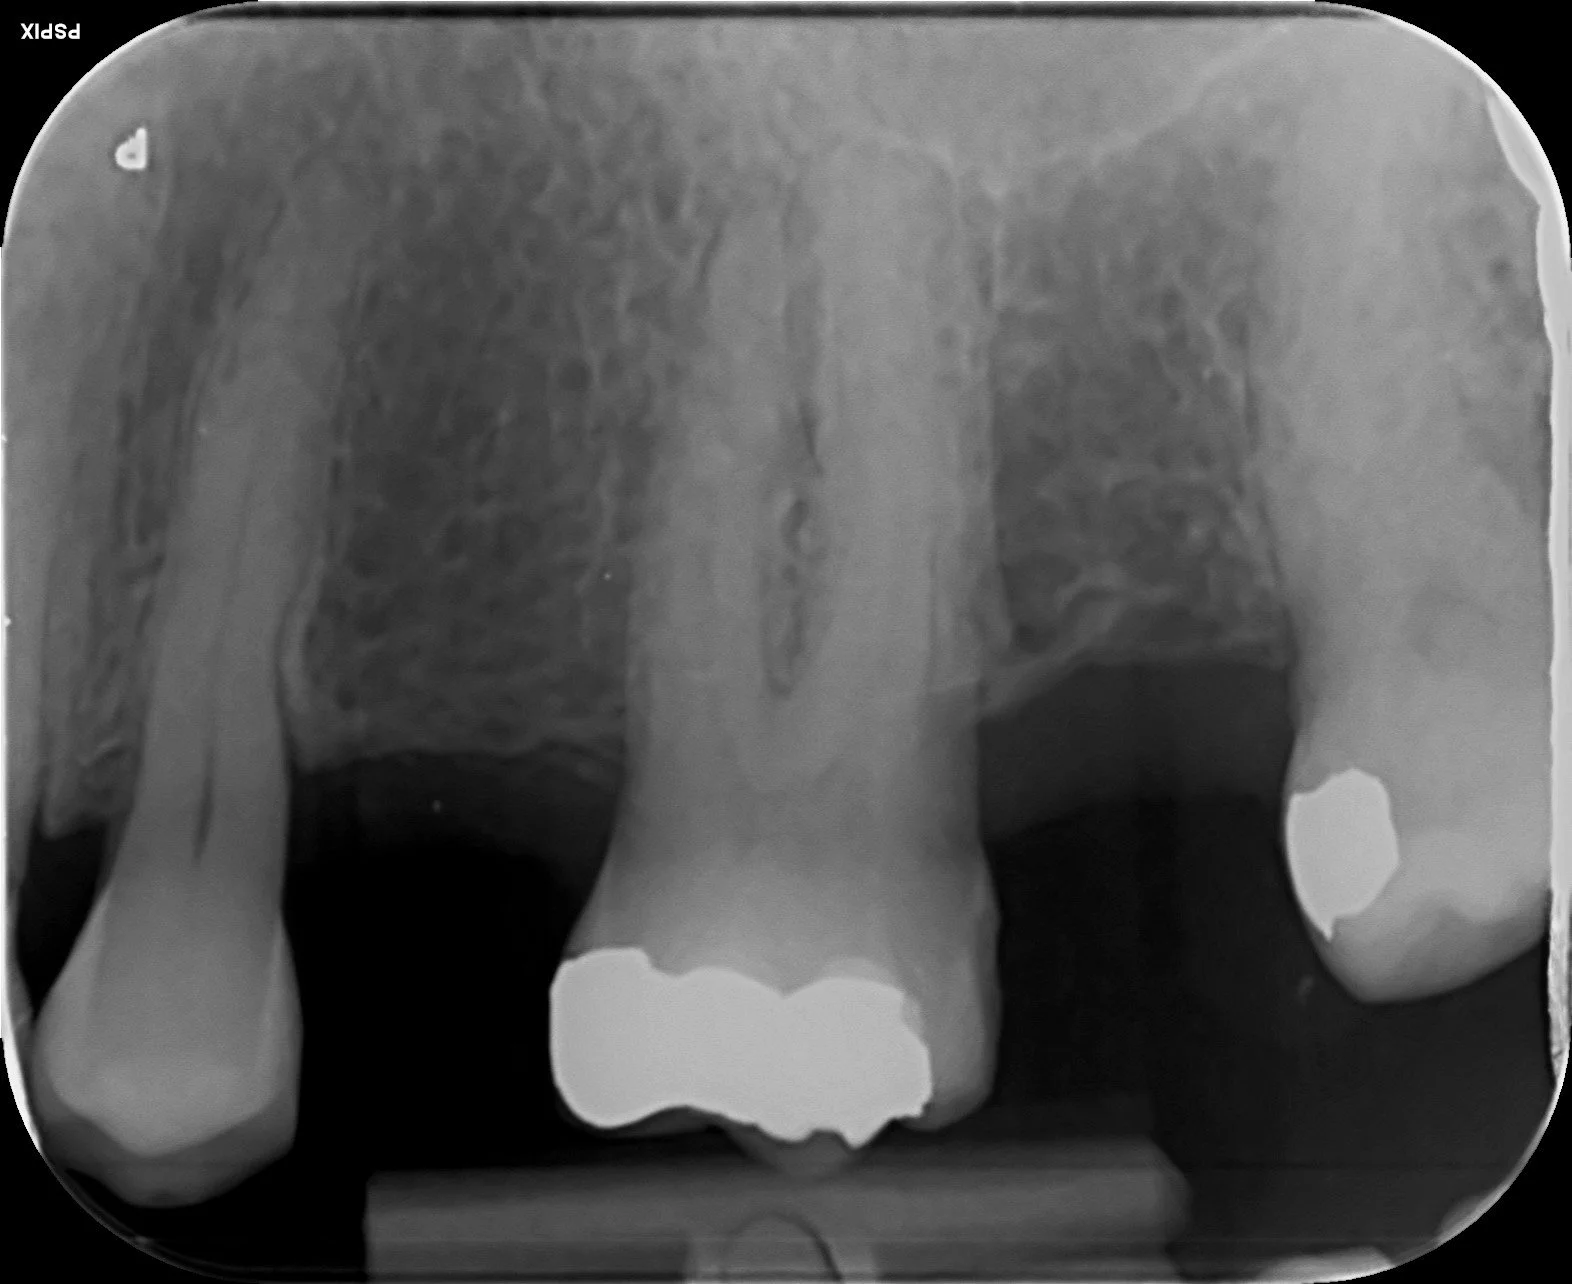

Root canal treatment of upper molar. Localisation of MB2 canal.